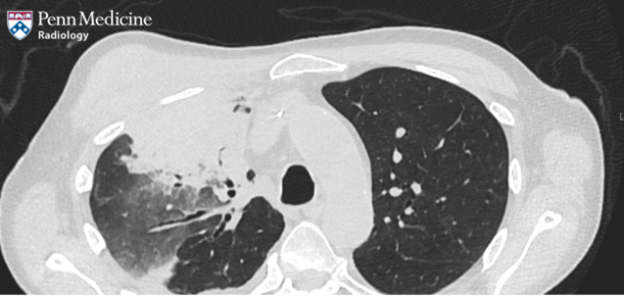

70-year-old man with fever and progressive hypoxia

An immunocompromised 70-year-old man with recurrent acute myeloid leukemia (AML), recent reinduction, presented with fever and progressive hypoxia despite empiric antibiotic therapy.